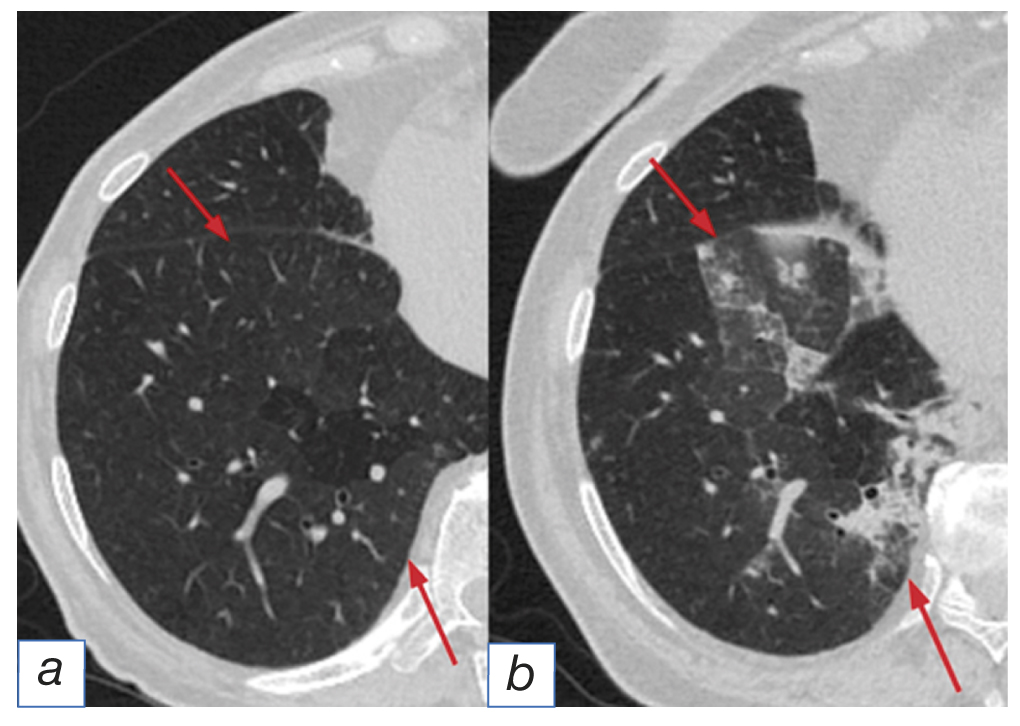

- the pattern of hypersensitivity pneumonitis [11] visualized as diffusely distributed induration of the pulmonary tissue (ground glass-type) with centrilobular nodules and “air trapping” upon exhaling (Fig. 3);

Fig. 3. The pattern of hypersensitivity pneumonitis: before (а) and after (b) immunotherapy (arrows).